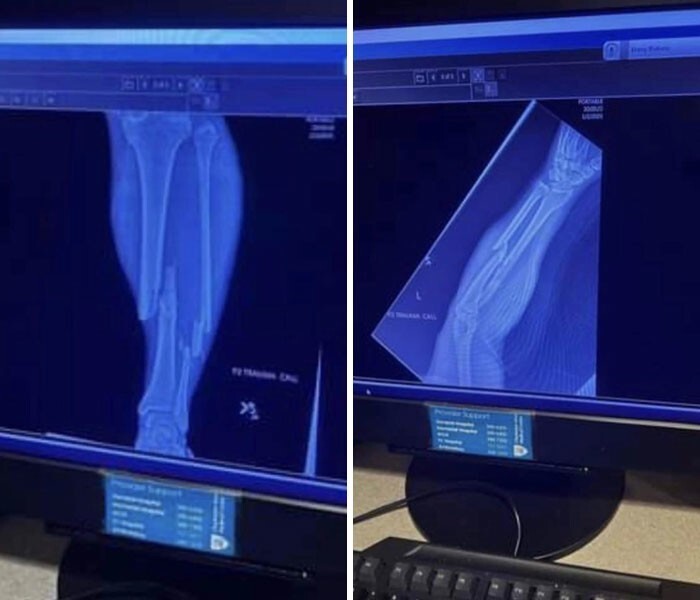

9. "Рентгенолог сказал, что перелома нет... Что-то я сомневаюсь"